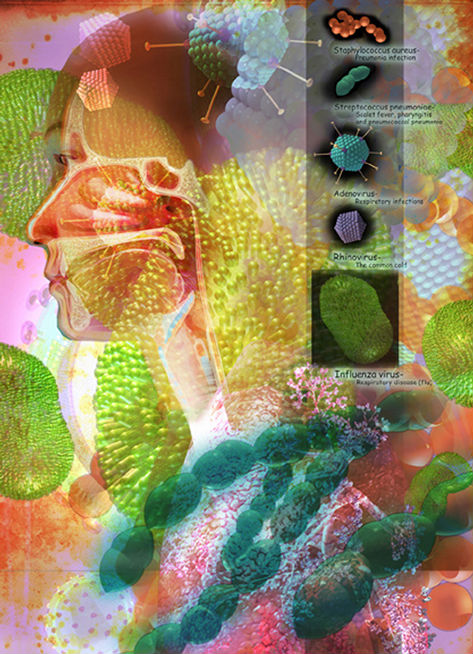

Collage for Nursing 2002, Magazine

Interpretation on the causes of respiratory infections and pneumonia

3D model collage for Elitra Pharmaceuticals

Interpretation showing essential genes in key pathogens genomics and the identification, development and commercialization of novel antimicrobial compounds.